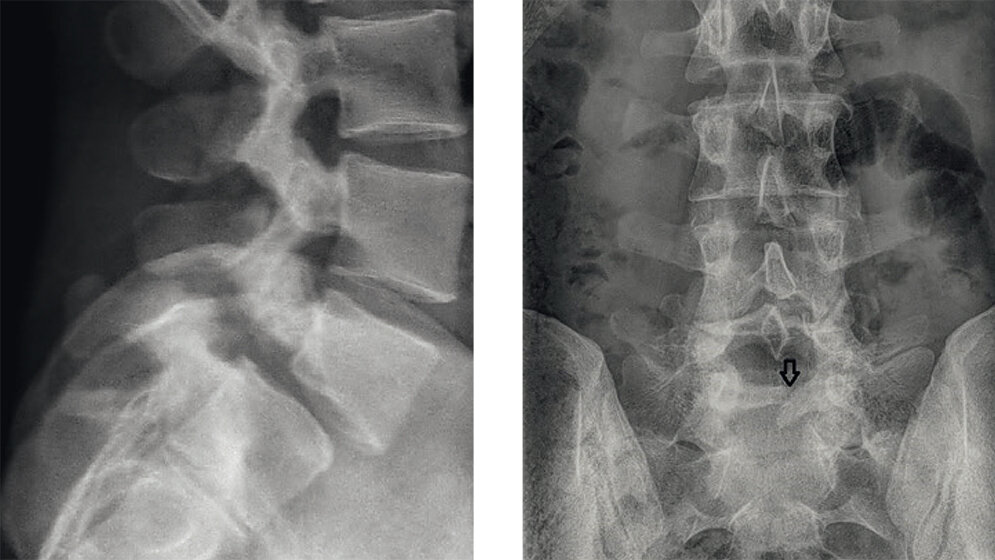

Anomalien und Normvarianten - Skelettale Veränderungen 3.8: Spondylolyse

Die Spondylolyse bei LWK 5 ist relativ häufig. Nicht alle Patienten entwickeln eine Symptomatik, zahlreiche Faktoren spielen dabei im Erwachsenenalter eine Rolle. Die Symptomatik nimmt mit dem Ausmaß der Bandscheibendegeneration zu.

Schlüsselwörter: Spondylolyse, Röntgen, CT, MRT